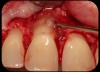

Then, too, are opportunities to prepare the site for regeneration by coupling therapies, applying an enamel matrix derivative, along with traditional bone grafts of demineralized freeze-dried bone allograft; potentially, gains in attachment with minimal probing depth and retained papilla may avoid the need for an implant (Figure 2 through Figure 7).

Severe periodontitis lesion.

Fig. 2

Facial bone loss and a mesial vertical defect.

Fig. 3

Application of enamel matrix derivative.

Fig. 4

Demineralized freeze-dried bone allograft.

Fig. 5

Evidence of clinical attachment gain.

Fig. 6

The 9-year postoperative radiograph.

Fig. 7